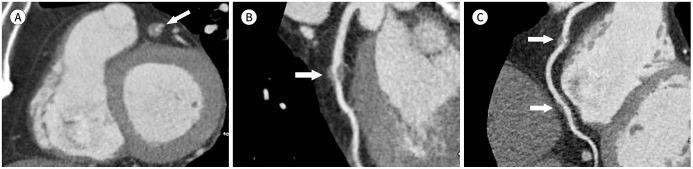

Immunoglobulin G4-related disease (IgG4-RD) is a chronic inflammatory condition involving multiple organs, including the salivary or lacrimal glands, orbit, pancreas, bile duct, liver, kidney, retroperitoneum, aorta, lung, and lymph nodes. It is histologically characterized by tissue infiltration with lymphocytes and IgG4-secreting plasma cells, storiform fibrosis, and obliterative phlebitis. In the thoracic involvement of IgG4-RD, mediastinal lymphadenopathy and perilymphangitic interstitial thickening of the lung are the most common findings. Peribronchovascular and septal thickening and paravertebral band-like soft tissue are characteristic findings of IgG4-RD. Other findings include pulmonary nodules or masses, ground-glass opacity, alveolar interstitial thickening, pleural effusion or thickening, mass in the chest wall or mediastinum, and arteritis involving the aorta and coronary artery. Radiologic differential diagnosis of various malignancies, infections, and inflammatory conditions is needed. In this review, we describe the imaging findings of IgG4-RD and the radiologic differential diagnoses in the thorax.

免疫球蛋白G4相关性疾病(IgG4-RD)是一种累及多个器官的慢性炎症性疾病,这些器官包括唾液腺或泪腺、眼眶、胰腺、胆管、肝脏、肾脏、腹膜后、主动脉、肺和淋巴结。其组织学特征为淋巴细胞和分泌IgG4的浆细胞浸润组织、席纹状纤维化和闭塞性静脉炎。在IgG4-RD累及胸部时,纵隔淋巴结肿大和肺淋巴管周围间质增厚是最常见的表现。支气管血管周围和小叶间隔增厚以及椎旁带状软组织是IgG4-RD的特征性表现。其他表现包括肺结节或肿块、磨玻璃影、肺泡间质增厚、胸腔积液或增厚、胸壁或纵隔肿块以及累及主动脉和冠状动脉的动脉炎。需要对各种恶性肿瘤、感染和炎症性疾病进行影像学鉴别诊断。在本综述中,我们描述了IgG4-RD的影像学表现以及胸部的影像学鉴别诊断。